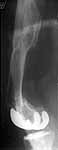

TAC> I can't actually see the osteotomy on either radiograph. Is it more proximal than we see in these radiographs or so well aligned as to be not visible?

The osteotomy was performed through the fracture site. See the attachment.